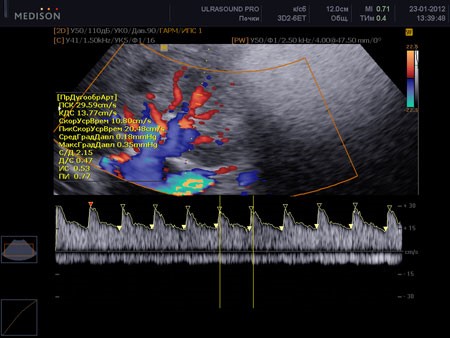

При дуплексном сканировании сосудов почек определяют количество почечных артерий, место их отхождения от аорты, взаимоотношения с нижней полой веной и верхней брыжеечной артерией. Исследуются и сравниваются скорости кровотока в аорте и почечных артериях. Изменение соотношения скоростей представляют важный диагностический материал, который позволяет заподозрить стеноз (сужение) устья артерий. В почке артерия делится на сегментарные ветви, междолевые, дуговые и внутридольковые артерии. При дуплексном сканировании проводится визуальная оценка распределения кровотока в почки и измеряются скоростные характеристики и коэффициенты, которые сравниваются с данными противоположной стороны.